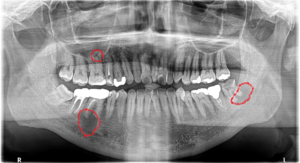

今回の患者さんは大きな病変が2つ、小さい病変が1つありました。

右下6番目と左下8番目の歯にウズラの卵くらいの大きな病変があります。右上6番にも小さな病変があります。

上の写真の赤丸が根尖病変です。